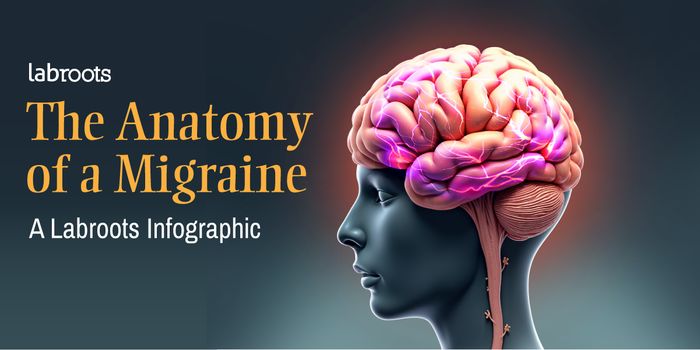

NOV 18, 2024InfographicsMigraines are one of the most well-known diseases around the world with approximately 40 percent of the global populace ...